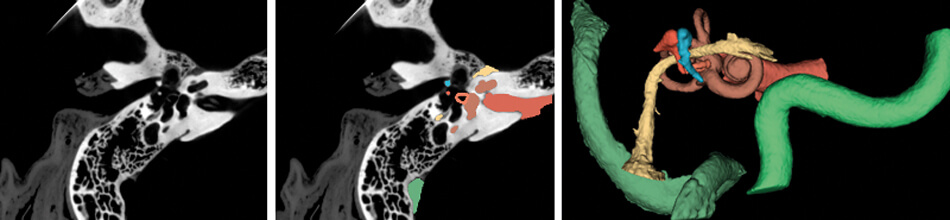

Figure 1. (Left) CT scan of the right temporal bone. (Middle) Structures of the temporal bone automatically segmented using a TensorFlow based deep learning algorithm. (Right) Three-dimensional model of the critical structures of the temporal bone to be used for surgical planning and simulation.

Images courtesy of the Auditory Biophysics Laboratory, Western University, London, Canada.

In addition to their role in general image classification, CNNs are likely to play a significant role in the introduction of machine learning in healthcare, especially in image-heavy specialties such as otolaryngology. For otologists, deep learning algorithms can already identify detailed temporal bone structures from CT images [3-6], segment intracochlear anatomy [7], and identify individual cochlear implant electrodes [8] (Figure 1); automatic analysis of critical structures on temporal bone scans have already facilitated patient-specific virtual reality otologic surgery [9] (Figure 2). Deep learning will likely also be critical in customised cochlear implant programming in the future.